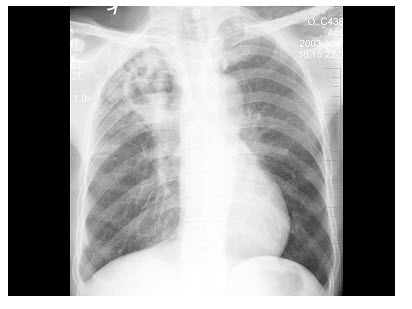

20、单项选择题

患儿,新生儿出生评分8分,出生约6小时后出现呼吸困难,进行性加重,并出现皮肤青紫及吸气性三凹征,胸片如下图所示,下列诊断正确的是()

A.肺出血

B.新生儿肺透明膜病

C.一侧肺不发育

D.吸入性肺炎

E.新生儿湿肺